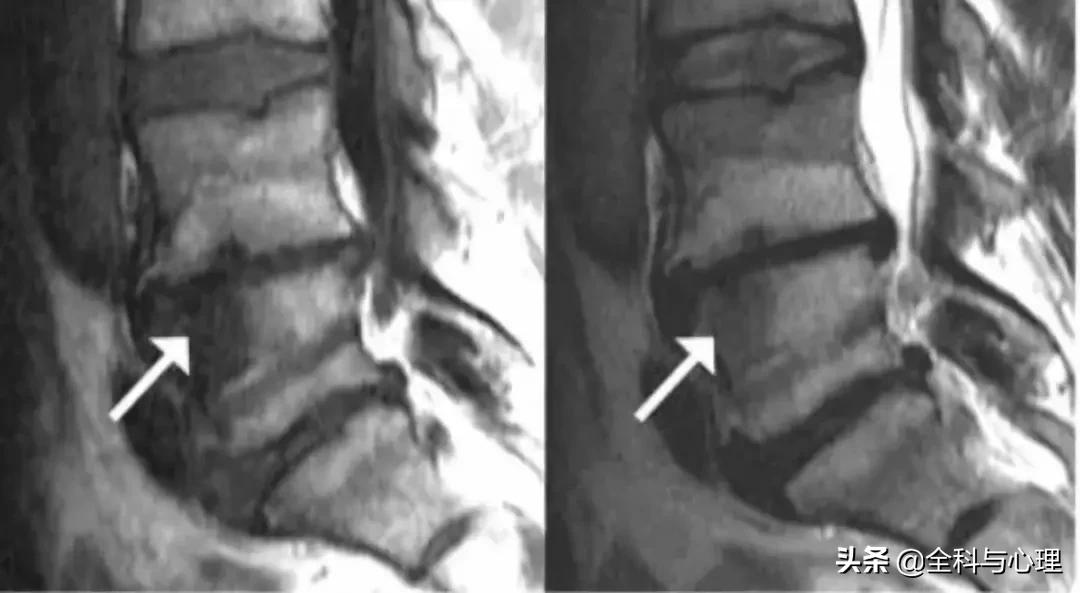

图示许莫氏结节(箭头所指),椎间盘造影后提示许莫氏结节为疼痛来源后行腰椎融合术

Modic 1 型 (T1 低信号,T2 高信号):终板区水肿表现

Modic 2 型 (T1 高信号,T2 等信号或轻度高信号):终板区脂肪沉积

Modic 3 型 (T1,T2 均低信号):终板区骨质硬化,单纯 3 型很少见。箭头所指为 3 型表现,L4,L5 椎体上缘的后半部分及 S1 上缘为 Modic 2 型改变。